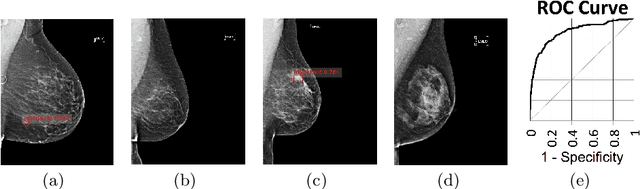

Abstract:State-of-the-art deep learning methods for image processing are evolving into increasingly complex meta-architectures with a growing number of modules. Among them, region-based fully convolutional networks (R-FCN) and deformable convolutional nets (DCN) can improve CAD for mammography: R-FCN optimizes for speed and low consumption of memory, which is crucial for processing the high resolutions of to 50 micrometers used by radiologists. Deformable convolution and pooling can model a wide range of mammographic findings of different morphology and scales, thanks to their versatility. In this study, we present a neural net architecture based on R-FCN / DCN, that we have adapted from the natural image domain to suit mammograms -- particularly their larger image size -- without compromising resolution. We trained the network on a large, recently released dataset (Optimam) including 6,500 cancerous mammograms. By combining our modern architecture with such a rich dataset, we achieved an area under the ROC curve of 0.879 for breast-wise detection in the DREAMS challenge (130,000 withheld images), which surpassed all other submissions in the competitive phase.